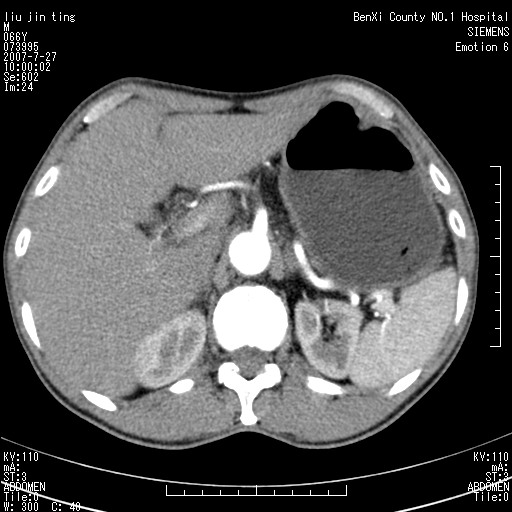

腹痛,背痛,无恶心呕吐,不黄,彩超示胰腺钩癌,ct扫描病灶平扫30-40hu,增强后动脉期40--60hu,静脉期50-68hu,真的是钩突上的么?您要试一试么?

沿着肠系膜上动脉呈匍匐性生长的软组织肿块,形态不规则,包绕肠系膜上动脉,呈明显强化,考虑来源于肠系膜的恶性肿瘤

沿着肠系膜上动脉呈匍匐性生长的软组织肿块,形态不规则,包绕肠系膜上动脉,呈轻-中度强化,考虑来源于肠系膜的恶性肿瘤。

钩突是正常的,只见腹膜后淋巴结的肿大,考虑淋巴瘤或转移可能。

支持!恶性纤维组织细胞瘤可能,与淋巴瘤及淋巴结转移鉴别(腹主动脉周围清晰,其他部位亦未见明显肿大淋巴结)。

后腹膜肿块,包围血管,考虑淋巴恶性病变,淋巴瘤或转移。